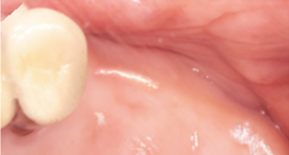

1. Before surgery